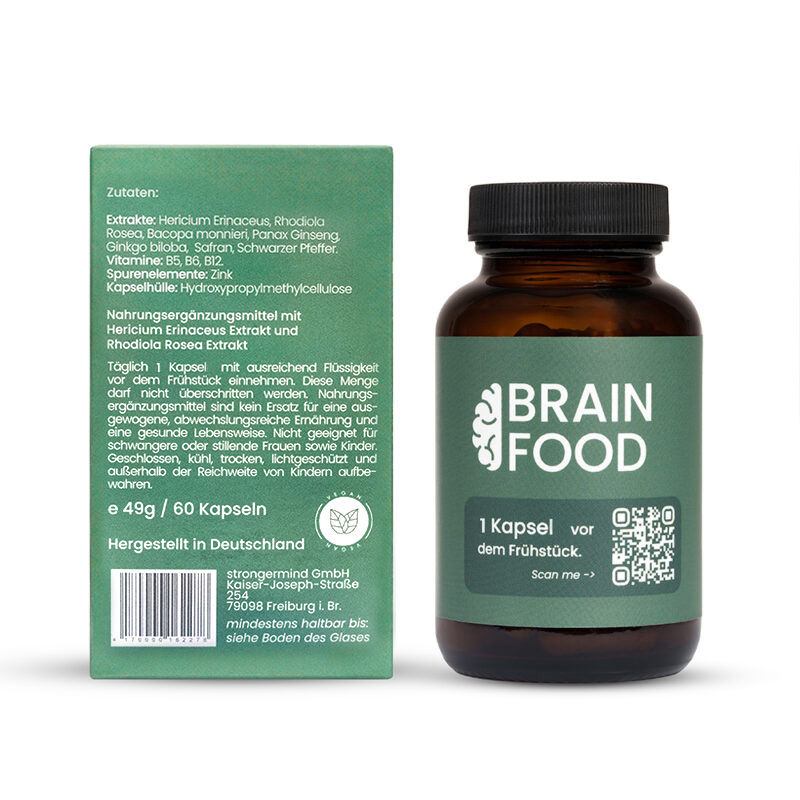

BrainFood enthält 7 verschiedene pflanzliche Extrakte. Jedes Extrakt ist hierbei darauf ausgelegt einen gezielten Aspekt der Kognition zu fördern. Die Wirkung der Extrakte wird unter anderem durch die Wachstumsfaktoren BDNF (brain derived neurotrophic factor) sowie NGF (neuronal growth factor) vermittelt. Neuronale Wachstumsfaktoren tragen zu einer vermehrten Synaptogenese also dem Bilden neuer Synapsen, sowie neuronalem Branching, dem Dendritenwachstum der Neuronen, bei. Das perfekte Zusammenspiel aus hochwertigen pflanzlichen Extrakten, allen wichtigen B-Vitaminen sowie Zink sorgt so für eine optimale und nachhaltig gesunde Gehirnfunktion. ²

| Hericium Erinaceus Extrakt | 200 mg | ** |

| davon Polysaccharide | 60 mg | ** |

| Rhodiola Rosa Extrakt | 165 mg | ** |

| davon Rosavine | 4,95 mg | ** |

| davon Salidroside | 1,65 mg | ** |

| Bacopa Monnieri Extrakt | 150 mg | ** |

| davon Bacoside | 75 mg | ** |

| Panax Ginseng Extrakt | 100 mg | ** |

| davon Ginsenoside | 20 mg | ** |

| Ginkgo biloba Extrakt | 60 mg | ** |

| davon Flavone | 14,4 mg | ** |

| davon Lactone | 3,6 mg | ** |

| Safran Extrakt | 15 mg | ** |

| davon Lepticrosalide | 0,53 mg | ** |

| Schwarzer Pfeffer Extrakt | 2,3 mg | ** |

| davon Piperin | 2,19 mg | ** |

| Vitamin B5 | 3 mg | 50% * |

| Vitamin B6 | 0,7 mg | 50% * |

| Vitamin B12 | 1,25 µg | 50% * |

| Zink | 1,66 mg | 17% * |